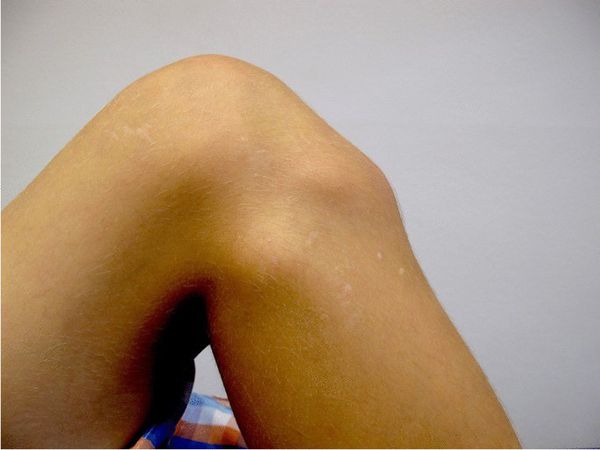

При частых сгибаниях коленного сустава в месте бугристисти большеберцовой кости может появиться твёрдый на ощупь бугорок. Кроме выпячивания пациента ничего не беспокоит.

![Бугорок под коленом [18]](/pimg3/privichniy-vivix-nadkolennika-A59DBCA.jpeg)

Болезнь Шляттера приводит к перестройке бугристости, нестабильности коленного сустава и напряжению мягких тканей ног, из-за чего у людей возникает боль под коленным суставом уже во взрослом возрасте.